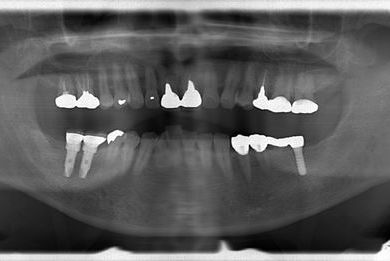

インプラントの症例写真 IMPLANT

インプラント治療

| 性別/年齢 | 男性 / 59歳 | ||||||||||||||||||||||||||||||||

| 主訴 | インプラント治療を検討中。 | ||||||||||||||||||||||||||||||||

| 治療方針 | 欠損部分インプラント治療により、機能的・審美的回復を行う。 | ||||||||||||||||||||||||||||||||

| 治療内容 | インプラント2本、ハイブリッドセラミック2本 | ||||||||||||||||||||||||||||||||

| 総治療費 | 738,675円 | ||||||||||||||||||||||||||||||||

| 治療期間 | 8ヶ月 |